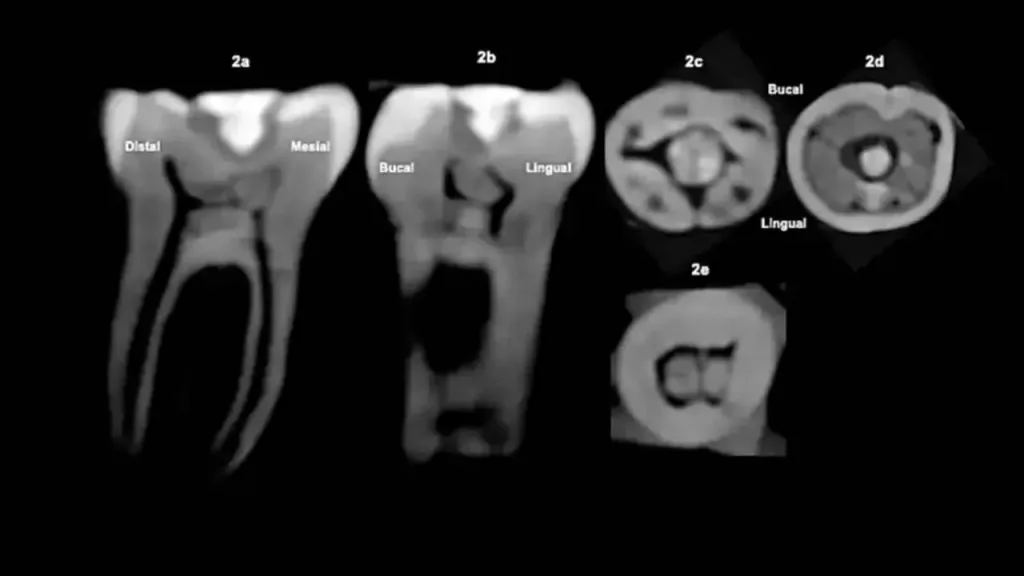

En el centro geométrico de la superficie se encuentra ubicada una incrustación de color verdoso, identificada como jadeíta o un material similar, fijada con un cemento. La piedra está completamente al ras, es decir, no sobresale y no molesta al morder.

Un empaste terapéutico: la cavidad donde se insertó la piedra es irregular, lo que sugiere que el tallado pudo hacerse sobre una lesión previa, quizá una caries, por lo que se habría eliminado tejido dañado y luego se habría sellado el hueco, aunque la tomografía no muestra un patrón de caries activa.